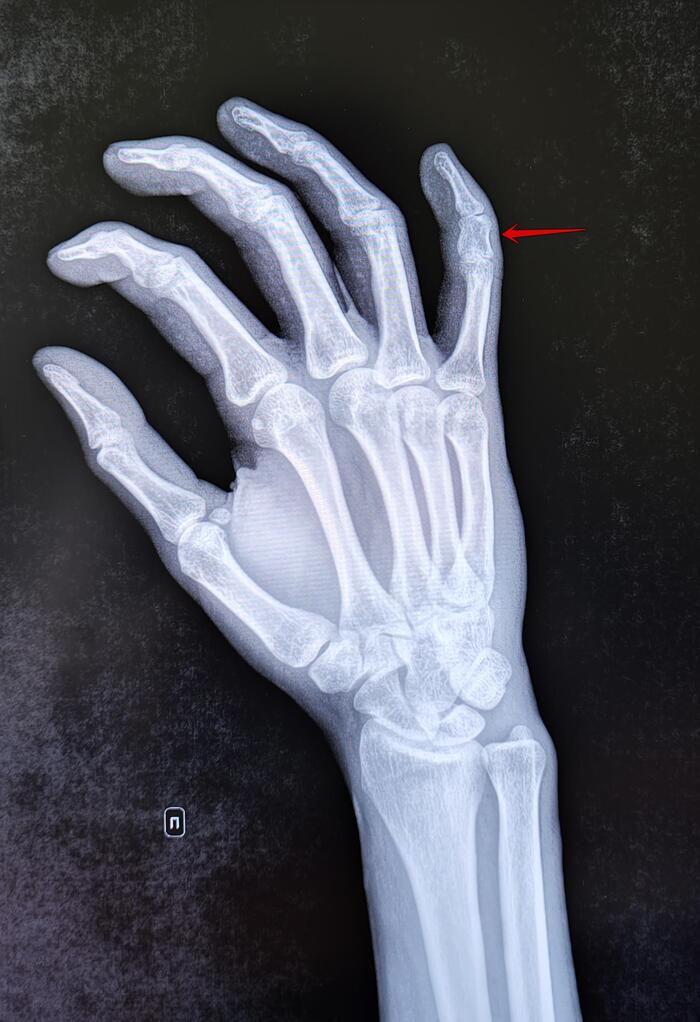

Брахидактилия

Это врождённая аномалия развития, характеризующаяся укорочением пальцев кистей и/или стоп из-за недоразвития или отсутствия фаланг.

На Р-граммах правой кисти в 2х проекциях: травматических, деструктивных изменений не выявлено. Структура костной ткани не изменена. Средняя фаланга пятого пальца укорочена, утолщена. По остальным отделам кисти-без явной костной патологии.

Заключение: Врожденная аномалия развития правой кисти- брахидактилия (брахифалангия) средней фаланги пятого пальца правой кисти.

Категория годности с данным диагнозом по ст.67(Отсутствие, деформации, дефекты кисти и пальцев), г) при наличии объективных данных без нарушения функций-Б3(годен к в/сл с незначительными ограничениями).